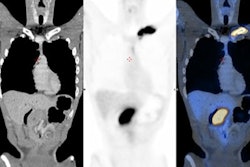

All patients showed metabolically active lesions in both lungs with FDG standard uptake values (SUV) between 2.0 and 12.7 (mean SUVmax of 4.2) and metabolically active mediastinal lymph nodes (mean SUVmax of 3.5, range 2.4-5.1) were noted in 13 (52%) patients, as well as significant CT lung findings.

A 71-year-old male diagnosed with COVID-19 in October 2020. After treatment, he was discharged from the hospital. He was readmitted to the hospital for respiratory failure in January 2021 and underwent F-18 FDG PET/CT. (A) Maximum intensity projection whole-body image and axial fused PET/CT show FDG-avid (SUVmax, 12.7) consolidation in the right lung (red arrow). Non-tracer-avid changes are noted in both lungs on CT. FDG-avid mediastinal lymph nodes (SUVmax, 4.4) (yellow arrow) were also noted. The patient was given steroids and pirfenidone for two months. He showed significant improvement in symptoms with no oxygen requirement. (B) Follow-up PET/CT reveals complete resolution of the lung lesion and non-avid residual fibrotic changes in both lungs (red arrow). Mediastinal lymph nodes also show a decrease in avidity (SUVmax, 2.5). Image courtesy of Yogita Khandelwal.Patients received methylprednisolone (a steroid) and pirfenidone (an antifibrotic drug), then underwent a follow-up scan between six and 12 weeks later to evaluate their response to treatment and assess residual lung damage.

Three patients died during the follow-up period due to respiratory septic shock, Khandelwal said. Among the 22 other patients, there was a significant decrease in the number, size, and "FDG avidity" of the previously seen lung lesions, she said.

Specifically, seven (32%) of these 22 patients were found to have active metabolic lesions in the lung parenchyma, with mean SUVmax dropping from 4.2 to 2.7. Also, five (23%) patients showed a mean SUVmax in metabolically active mediastinal lymph nodes dropping from 3.5 to 3.2.